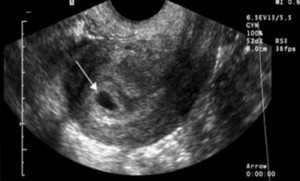

На основании результатов УЗИ выделяют два типа неразвивающейся беременности: анэмбриония (отсутствие эмбриона в плодном яйце, эмбрион либо не сформировался изначально, либо его развитие остановилось на ранних сроках беременности, не позже 5-ой недели гестации) и гибель эмбриона (плода). Различают анэмбрионию 1-го (зародыш не визуализируется, величина диаметра плодного яйца не превышает 2,0–2,5 см, размеры матки соответствуют 5–7-й неделе гестации, наблюдается отставание размеров матки и плодного яйца от срока беременности и прекращение их роста при наблюдении в динамике) и 2-го типа (наблюдается отсутствие эмбриона или его остатков в виде позвоночного сгиба, однако плодное яйцо растет с нормальной скоростью, не идентифицируется закладка ворсинчатого хориона, наблюдается наличие плодного яйца и эмбриона в полости матки без признаков жизнедеятельности).

Наиболее информативным методом диагностики неразвивающейся беременности является УЗИ, которое позволят поставить диагноз еще до появления жалоб. При ультразвуковом исследовании выявляется отсутствие эмбриона в полости плодного яйца после седьмой недели гестации или отсутствие сердцебиения плода. Отсутствие сердцебиений плода — не единственный и не обязательный признак неразвивающейся беременности, так как на малых сроках беременности сердцебиений ещё не наблюдают.

Для ранней диагностики замершей беременности проводят трансвагинальное УЗИ в сочетании с определением уровня β-ХГЧ (β-хорионический гонадотропин). В качестве дополнительных тестов с помощью иммуноферментного анализа определяют в сыворотке крови уровни маркеров: β –ХГЧ (содержание при замершей беременности снижено в 3–9 раз), α-фетопротеин (АФП, содержание при замершей беременности в 1,5–4 раза), трофобластический β1-гликопротеин (содержание при замершей беременности снижено в 6–18 раз), плацентоспецифический α1-микроглобулина (содержание при замершей беременности в 2,5 раза выше нормы), плацентарный лактоген (ПЛ) (содержание при замершей беременности снижено в 1,8–2,7 раза), содержание прогестерона при неразвивающейся беременности может сохраняться на относительно высоком уровне, а уровень эстрадиола резко снижается. Для коррекции возможных нарушений системы гемостаза до прерывания беременности необходимо осуществлять тщательный контроль системы свёртывания крови. Анализ крови у женщин с замершей беременностью выявляет увеличение концентрации моноцитов, уменьшение концентрации базофилов и эозинофилов и повышение уровня СОЭ.